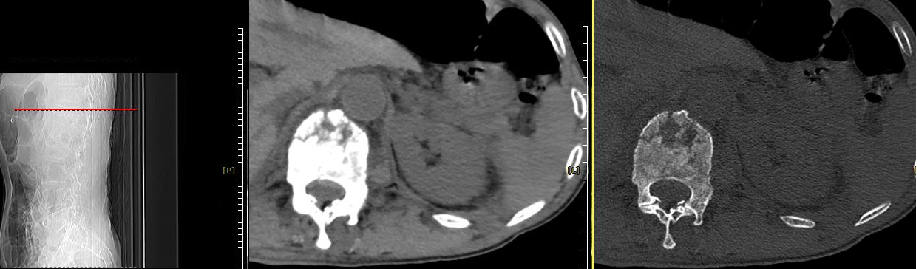

二、CT:看清骨折细节的 “透视眼”

骨折类型放大镜:

鉴别“压缩骨折” 与 “爆裂骨折”:爆裂骨折的椎体后壁破裂,骨块可能突入椎管,此时需谨慎选择手术方式,避免骨水泥渗漏风险。 -

显示椎弓根骨折、椎体裂隙征(真空征),帮助判断骨水泥填充难度。

接上例患者王某,CT 发现L1椎体后壁完整,但存在 “椎体裂隙征”(提示骨折未愈合),且椎弓根形态正常,适合行经皮椎体成形术(PVP)。若 CT 显示后壁破裂,则可能需改用球囊扩张椎体后凸成形术(PKP),通过球囊撑开复位减少渗漏风险。